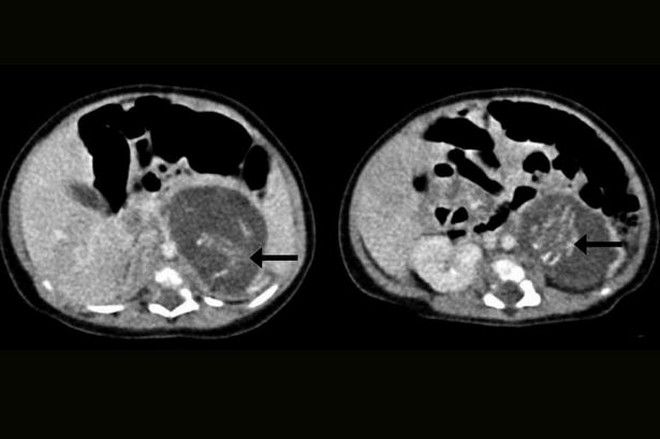

Το μωρό που γεννήθηκε στο Χονγκ Γκογκ, στο νοσοκομείο Queen Elizabeth, κυοφορούσε δυο έμβρυα, το ένα 14.2 γραμμαρίων και το άλλο 9.3 γραμμαρίων. Οι γιατροί αναφέρουν πως πρόκειται για μια πολύ σπάνια περίπτωση και πως τα δυο έμβρυα που εντοπίστηκαν στην κοιλιακή χώρα του νεογέννητου είχαν καταφέρει να αναπτυχθούν μερικώς, καθώς είχαν πόδια, χέρια και πλευρά.

Το κοριτσάκι υποβλήθηκε σε πολύωρη επέμβαση, που στέφθηκε με επιτυχία και κατάφερε να πάρει εξιτήριο από το νοσοκομείο μετά από οκτώ ημέρες, ενώ το περιστατικό καταγράφηκε στο επιστημονικό ιατρικό περιοδικό Hong Kong Medical Journal.